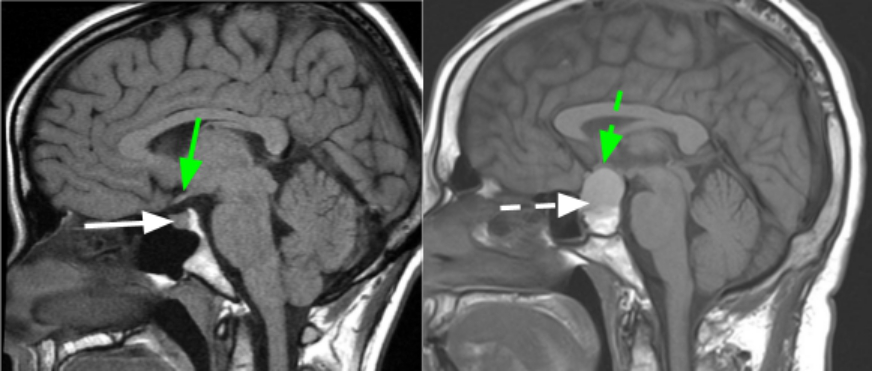

在西方发达国家,垂体腺瘤的优选手术治疗是神经内镜手术下经鼻入路(EEA),切除肿瘤。这种创新的、微创的技术利用鼻子和鼻腔作为自然通道,进入难以触及或以前无法手术的肿瘤。EEA具有创伤小、美观性好、等优点。但是神经内镜手术也存在的挑战,神经内镜手术一般是需要两个医生配合,很考验医生的默契,一不小心,便会造成失误。